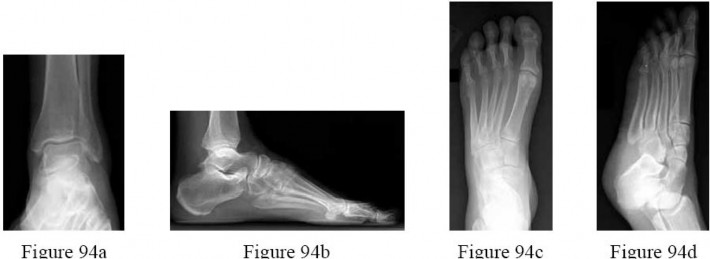

Figures 41a through 41c are the radiographs and Figure 41d is the biopsy specimen of a 14-year-old girl who has had increasing foot pain for several months. What is the most likely diagnosis? ---

Aneurysmal bone cysts frequently occur in the first two to three decades of life. Patients report pain and a slow-growing lesion. Radiographs show an expansile lesion with septae or striations.Treatment is usually curettage and grafting of the lesion. In the foot, unicameral bone cysts are seen most frequently in the calcaneus, and are usually incidental findings rarely requiring treatment. Infection or acute osteomyelitis typically shows lucency of bone, periosteal reaction, and a permeative pattern on radiographs.

Patients often have systemic complaints as well. Giant cell tumor is usually seen in the epiphysis of long bone with radiographs revealing a radiolucent lesion with a small rim of reactive bone.